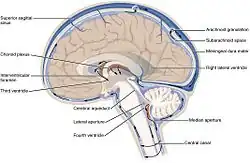

Każda z obu półkul mózgu zawiera w sobie jedną komorę boczną posiadającą łukowaty kształt, przypominający przechyloną nieco w dół literę „C”. W komorach bocznych wyróżnia się rogi przednie (cornu anterius ventriculi lateralis) sięgające do płatów czołowych, rogi dolne (cornu inferius) w płatach skroniowych, rogi tylne (cornu posterius) w płatach potylicznych oraz części środkowe. Komory boczne poprzez otwory międzykomorowe (foramina intraventricularia) łączą się z leżącą nieco niżej, ale położoną centralnie komorą III, znajdującą się częściowo w obrębie międzymózgowia. W tylnej części komory III rozpoczyna się wąski kanał – wodociąg mózgu, który nie zawiera splotu naczyniówkowego i przebiegając przez śródmózgowie łączy się z leżącą jeszcze niżej, również w linii środkowej, komorą IV. Ostatnia z komór znajduje się pomiędzy tylną częścią pnia mózgu a móżdżkiem. Komora IV posiada dwa otwory boczne (aperturae laterales ventriculi quarti) oraz jeden nieparzysty otwór pośrodkowy (apertura mediana ventriculi quarti), przez które płyn mózgowo-rdzeniowy przechodzi do przestrzeni podpajęczynówkowej.

Komory mózgu wypełnione są płynem mózgowo-rdzeniowym, który obmywa i amortyzuje mózg oraz rdzeń kręgowy wewnątrz struktur kostnych. Płyn jest produkowany przez wyspecjalizowane komórki wyściółki w splocie naczyniówkowym, który znajduje się we wszystkich elementach układu komorowego prócz wodociągu oraz tylnych rogów i przednich rogów komór bocznych. Płyn mózgowo-rdzeniowy przepływa z komór bocznych, poprzez otwory Monro, do komory trzeciej, a następnie przez wodociąg Sylwiusza do komory czwartej położonej w pniu mózgu. Z komory czwartej płyn mózgowo-rdzeniowy może przepłynąć do kanału środkowego rdzenia kręgowego lub do przestrzeni podpajęczynówkowej poprzez trzy nieduże otwory: pośrodkowy (Magendiego) i dwa boczne (Luschki).

Płyn następnie przepływa wokół zatoki strzałkowej górnej i jest reabsorbowany przez ziarnistości pajęczynówki do zatok opony twardej. Płyn mózgowo-rdzeniowy w rdzeniu kręgowym może płynąć aż do cysterny lędźwiowej, umiejscowionej blisko końca rdzenia kręgowego, wokół ogona końskiego, gdzie przeprowadza się nakłucie lędźwiowe.